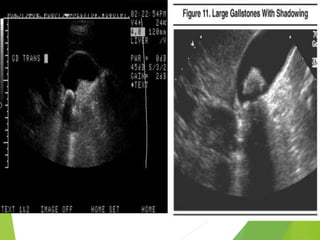

ACUTE CHOLECYSTITIS

Transverse

ultrasound

image (with

color flow)

thickening of

the gallbladder

wall (two-head

arrow),

distended

gallbladder.

Coronal CT image performed ,reveals gas (arrow) in the gallbladder lumen, marked

thickening of the gallbladder wall (double-head arrow), distention of gallbladder,

enhancement of gallbladder wall (arrowheads). Conglomerate mass in the gallbladder

wall represents sludge. Findings are consistent with emphysematous cholecystitis.